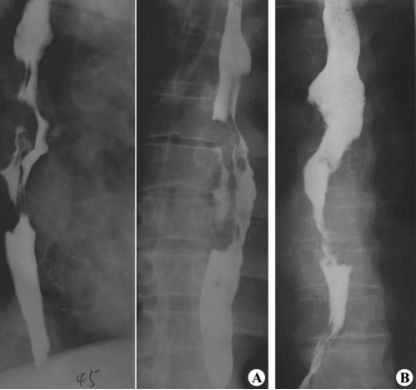

贲门失弛缓:鸟嘴征。

中度贲门失迟缓

重度贲门失迟缓